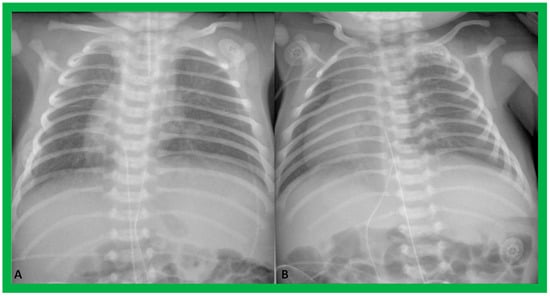

Figure 4. Chest X-rays of two neonates with their hearts in the middle of the chest, mesocardia. (A) The liver is visualized transversely in the abdomen; no gas bubble of the stomach (St) is seen. Therefore, visceroatrial situs cannot be determined with these findings. (B) The gaseous opacity of the St is visualized on the left side of the abdomen, and the liver (Li) is seen on the right, suggesting situs solitus. Reproduced from reference [4].

Figure 9. Chest roentgenograms of two babies with dextrocardia demonstrating liver across the entire abdomen. These babies were later diagnosed with asplenia syndrome. Umbilical venous and arterial catheters (not labeled) are seen in both (A) and (B).